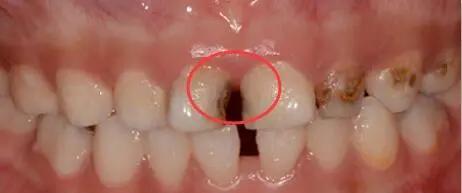

早期邻面龋的症状主要有牙齿邻面颜色发黑,因为在邻面,不容易被发现,此外,无其他特别的症状。

随着邻面龋的进一步发展,肉眼观察牙齿邻面颜色暗黑,对光线的透射性减弱。X线显示牙齿邻面出现三角形低密度阴影。牙齿遇冷热酸甜等刺激产生酸痛,经常出现大量食物残渣嵌塞,伴有腐臭味。龋损进一步扩展时,会发生颌面牙体组织的折裂。